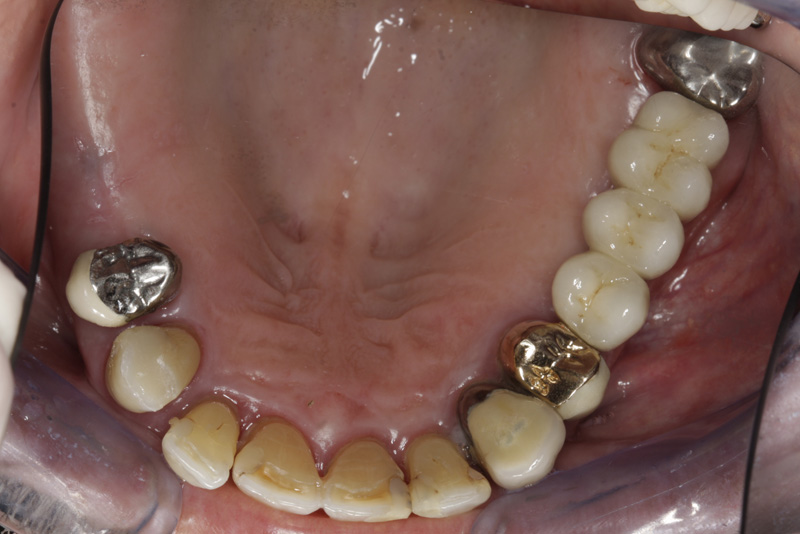

V případě chybění většího počtu zubů v postranních úsecích čelistí je možné ošetření pomocí implantátů, které nahradí ošetření pomocí snímacích náhrad kotvených na zbývajících zubech nebo patře.

Podmínkou je opět dostatečné množství kosti.

Protetické řešení může být pomocí můstku, který je kotvený na implantátech nebo pomocí jednotlivých korunek na implantátech.

V zásadě je možné do těchto můstků zařadit i přirozené zuby, zejména pokud je potřeba tyto zuby ošetřit proteticky - korunkami. Korunky nebo můstky mohou být na implantáty nacementovány nebo přišroubovány.

Zdravé zuby zůstanou zachovány a přitom náhrady jsou pevné, jako na vlastních zubech